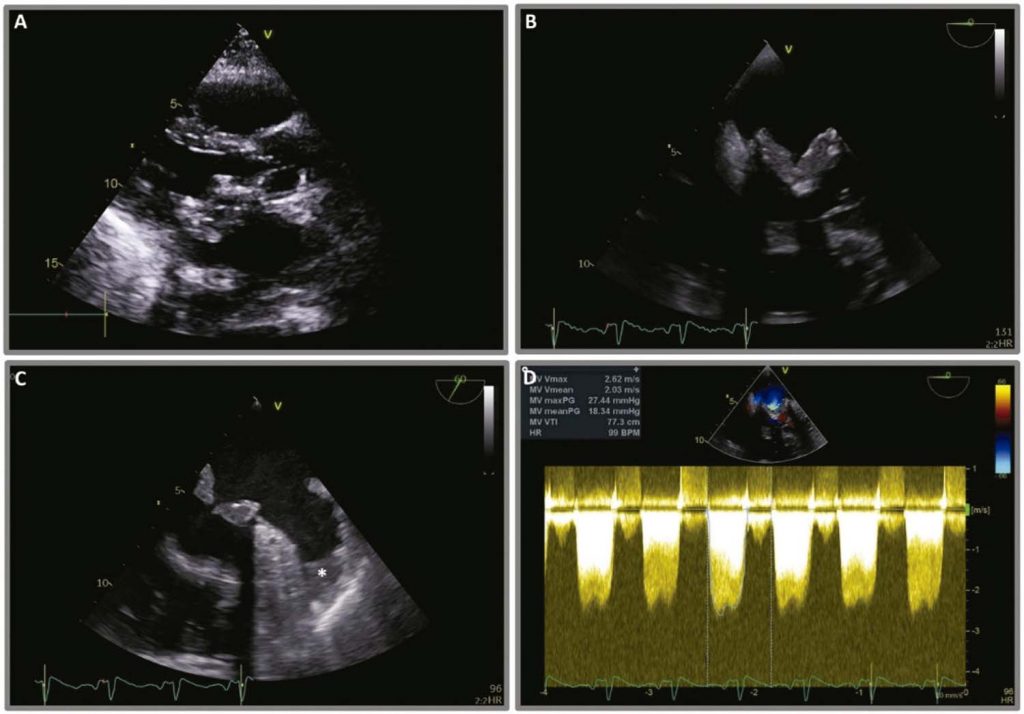

Trombose Tardia de Prótese Biológica em Posição Mitral com Apresentação com Obstrução Significativa e Insuficiência Cardíaca Aguda

A trombose de prótese valvar biológica (TPVB) tem uma incidência que varia entre 0,5% e 6%. No entanto, ela provavelmente é subnotificada devido às limitações técnicas da ecocardiografia transtorácica (ETT) 2D e ao desconhecimento da condição.

Relatamos o caso de um homem de meia-idade que foi internado com insuficiência cardíaca aguda e foi diagnosticado com TPVB. O reconhecimento do quadro e a adoção imediata da anticoagulação parenteral permitiram o restabelecimento do funcionamento normal da válvula biológica, evitando estratégias invasivas.